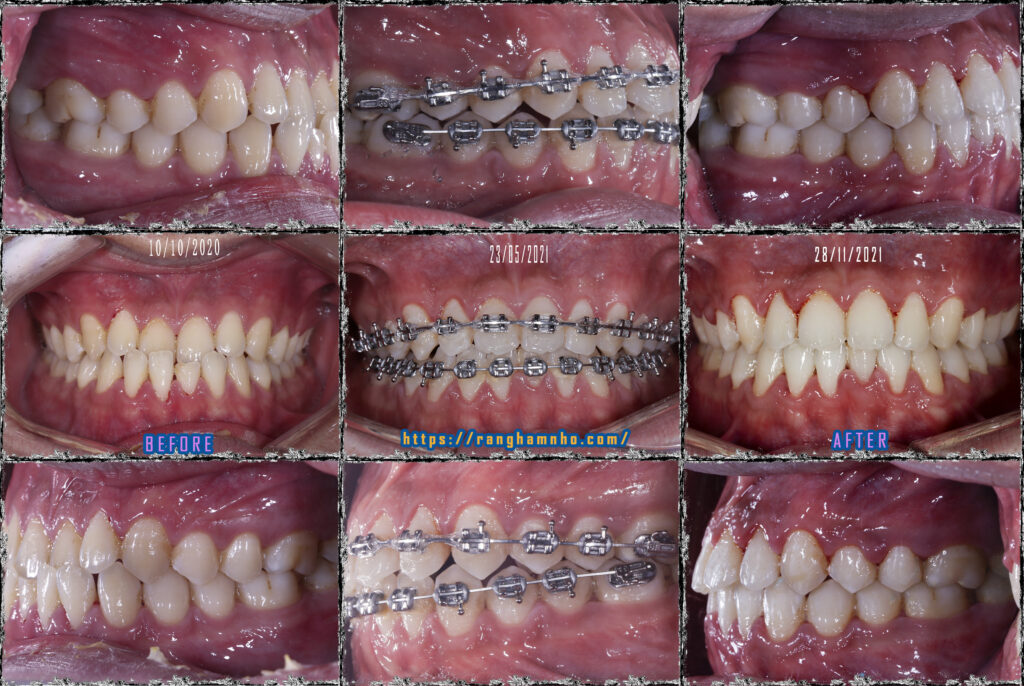

Cũng là khớp cắn ngược nhưng xét về độ khó thì khớp cắn ngược do răng điều trị sẽ đỡ vất vả hơn cắn ngược do xương nhiều. Bệnh nhân nam sinh năm 1998 đến khám niềng với mong muốn cải thiện nụ cười móm.

Bệnh nhân chọn niềng mắc cài truyền thống dây cung thẳng liên tục. Giai đoạn đầu san bằng sắp đều cung răng hai hàm, giai đoạn 2 vượt khớp tạo cắn chùm cắn chìa dương. Giai đoạn cuối tinh chỉnh khớp căn, duy trì và tháo niềng.

Kết quả tháo niềng sau 1.5 năm, thay đổi tích cực trên cả lâm sàng và trên phim xquang.